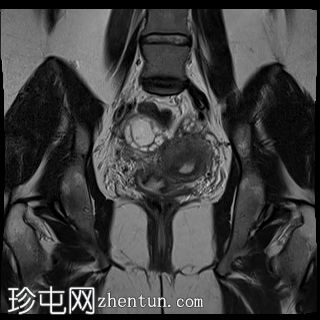

冠状位

T2加权像

双侧卵巢位置接近(卵巢相吻),左侧卵巢内可见一边界清晰的囊性病变,大小约3.1 × 2.7 × 2.9 cm,T1加权像呈高信号,T2加权像可见暗点征及内部暗点征。以上MRI特征符合卵巢子宫内膜异位囊肿的诊断。

右侧卵巢可见一囊肿,大小约为 2.8 × 2.0 × 2.2 cm,T1 加权像呈高信号,囊内可见液-液平面,提示囊内含有不同时期的出血性物质。由于对侧卵巢存在典型的子宫内膜异位囊肿,且该囊肿无强化,影像学表现强烈提示为另一子宫内膜异位囊肿。

双侧卵巢均可见多个小卵泡。

双侧卵巢囊性病变,MRI 表现符合子宫内膜异位囊肿的特征,左侧较大。未见强化壁结节或实性成分,提示无恶性转化。